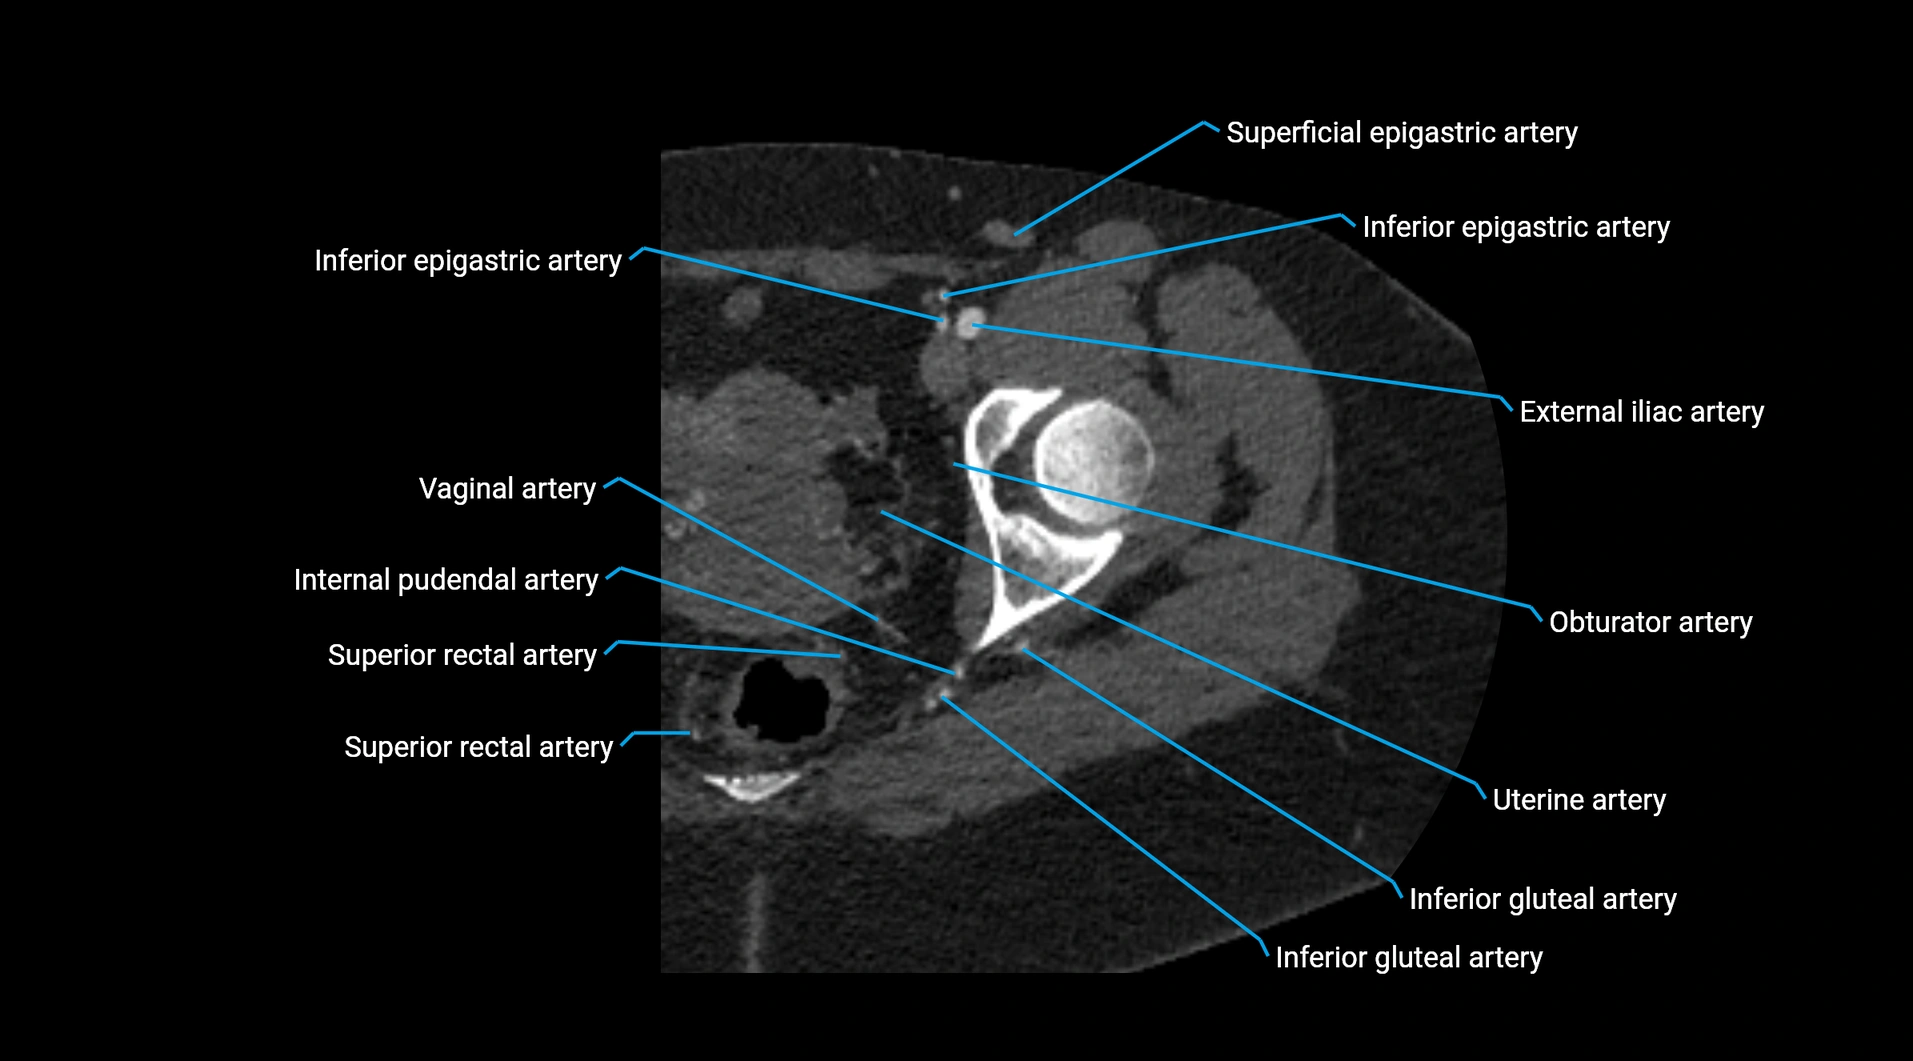

CT images

image

Contrast-enhanced CT (CTA):

• Gold standard for abdominal aortic imaging

• Provides excellent detail of lumen, wall, aneurysm, thrombus, and branch vessels

• Multiplanar and 3D reconstructions help in aneurysm measurement, stent graft planning, and dissection evaluation